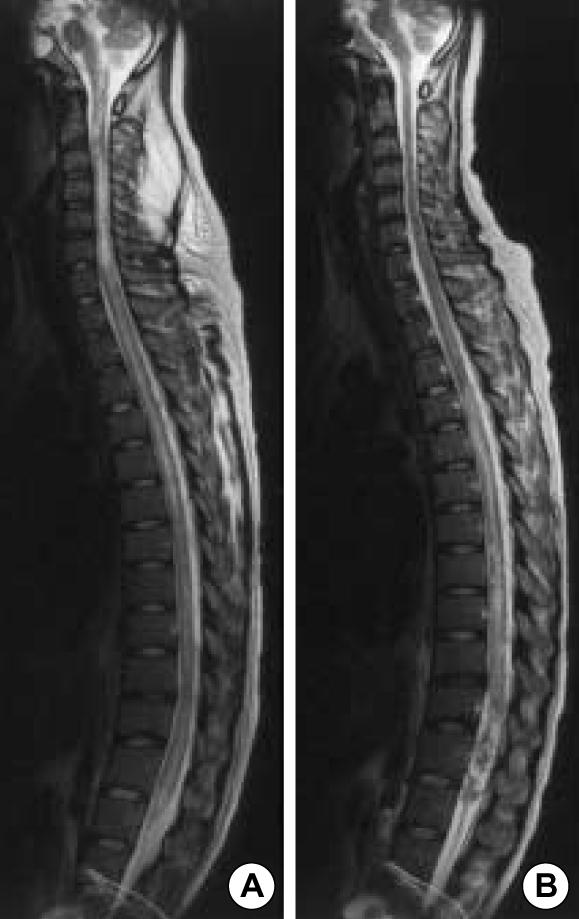

Transverse myelitis (TM) extending from midbrain to the entire spinal cord accompanied by internuclear ophthalmoplegia is extremely rare but cause serious central nervous system complications in patients with systemic lupus erythematosus. We report a case of a 28-yr-old woman with TM extending from the midbrain to the conus medullaris longitudinally and internuclear ophthalmoplegia associated with systemic lupus erythematosus. Her neurological symptoms had an abrupt catastrophic onset and rapidly progressed to respiratory failure within 24 hr. Bilateral internuclear ophthalmoplegia was also followed by TM. Brain MR images showed definite brainstem lesions, which were deeply associated with internuclear ophthalmoplegia, and diffuse signal changes in the whole spinal cord, medulla, pons and midbrain. Clinical improvement of her ophthalmoplegia and of neurological dysfunction of the upper extremities was noted after prompt and aggressive treatment with intravenous pulsed methylprednisolone and cyclophosphamide. However, the neurological dysfunction of the lower limbs and bladder and colon paralysis were almost unchanged until six months passed.

横贯性脊髓炎(TM)从脑干延伸至整个脊髓并伴有核间性眼肌麻痹极为罕见,但会在系统性红斑狼疮患者中引发严重的中枢神经系统并发症。我们报告一例28岁女性,其TM纵向从脑干延伸至脊髓圆锥,且伴有与系统性红斑狼疮相关的核间性眼肌麻痹。她的神经症状呈突发灾难性发作,并在24小时内迅速进展为呼吸衰竭。双侧核间性眼肌麻痹也先于TM出现。脑部磁共振成像显示明确的脑干病变,与核间性眼肌麻痹密切相关,以及整个脊髓、延髓、脑桥和中脑的弥漫性信号改变。在静脉注射脉冲甲基强的松龙和环磷酰胺进行迅速且积极的治疗后,她的眼肌麻痹和上肢神经功能障碍有了临床改善。然而,直到六个月过去,下肢神经功能障碍以及膀胱和结肠麻痹几乎没有变化。